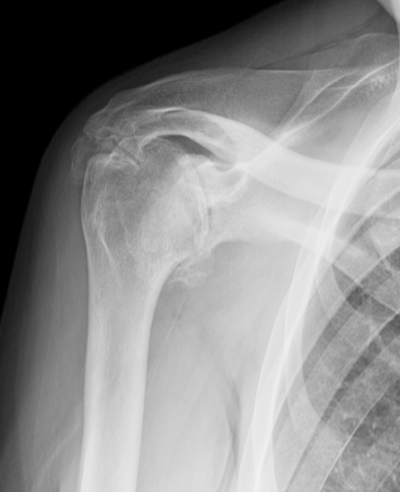

Rotator Cuff Arthropathy

Arthritic Shoulder